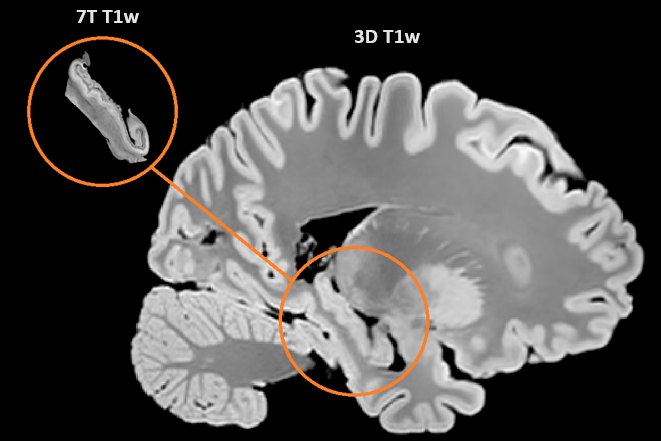

We did a thing! Our first results from "The Douglas Bell Canada Brain Bank Post-mortem Brain Imaging Protocol" biorxiv.org/content/10.110… Yasharz Liana Guerra Jérémie Fouquet roqa moqadam Zaki Alasmar Mallar Chakravarty Douglas Research Centre